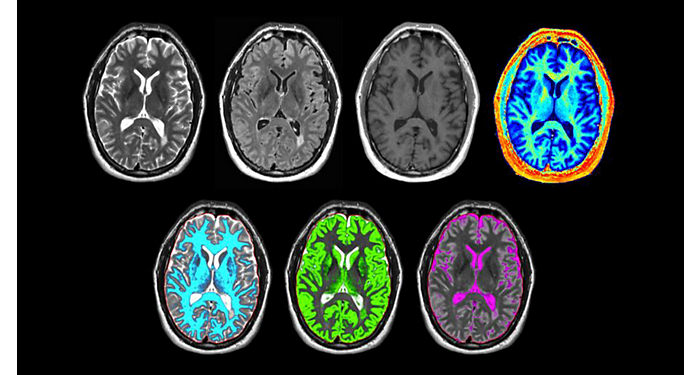

Centro médico de la Universidad de Vermont, EE. UU.

Protocolos cerebrales de UVM actualizados con los últimos métodos

UVM aprecia los últimos métodos neurológicos de resonancia magnética para el diagnóstico y el flujo de trabajo.